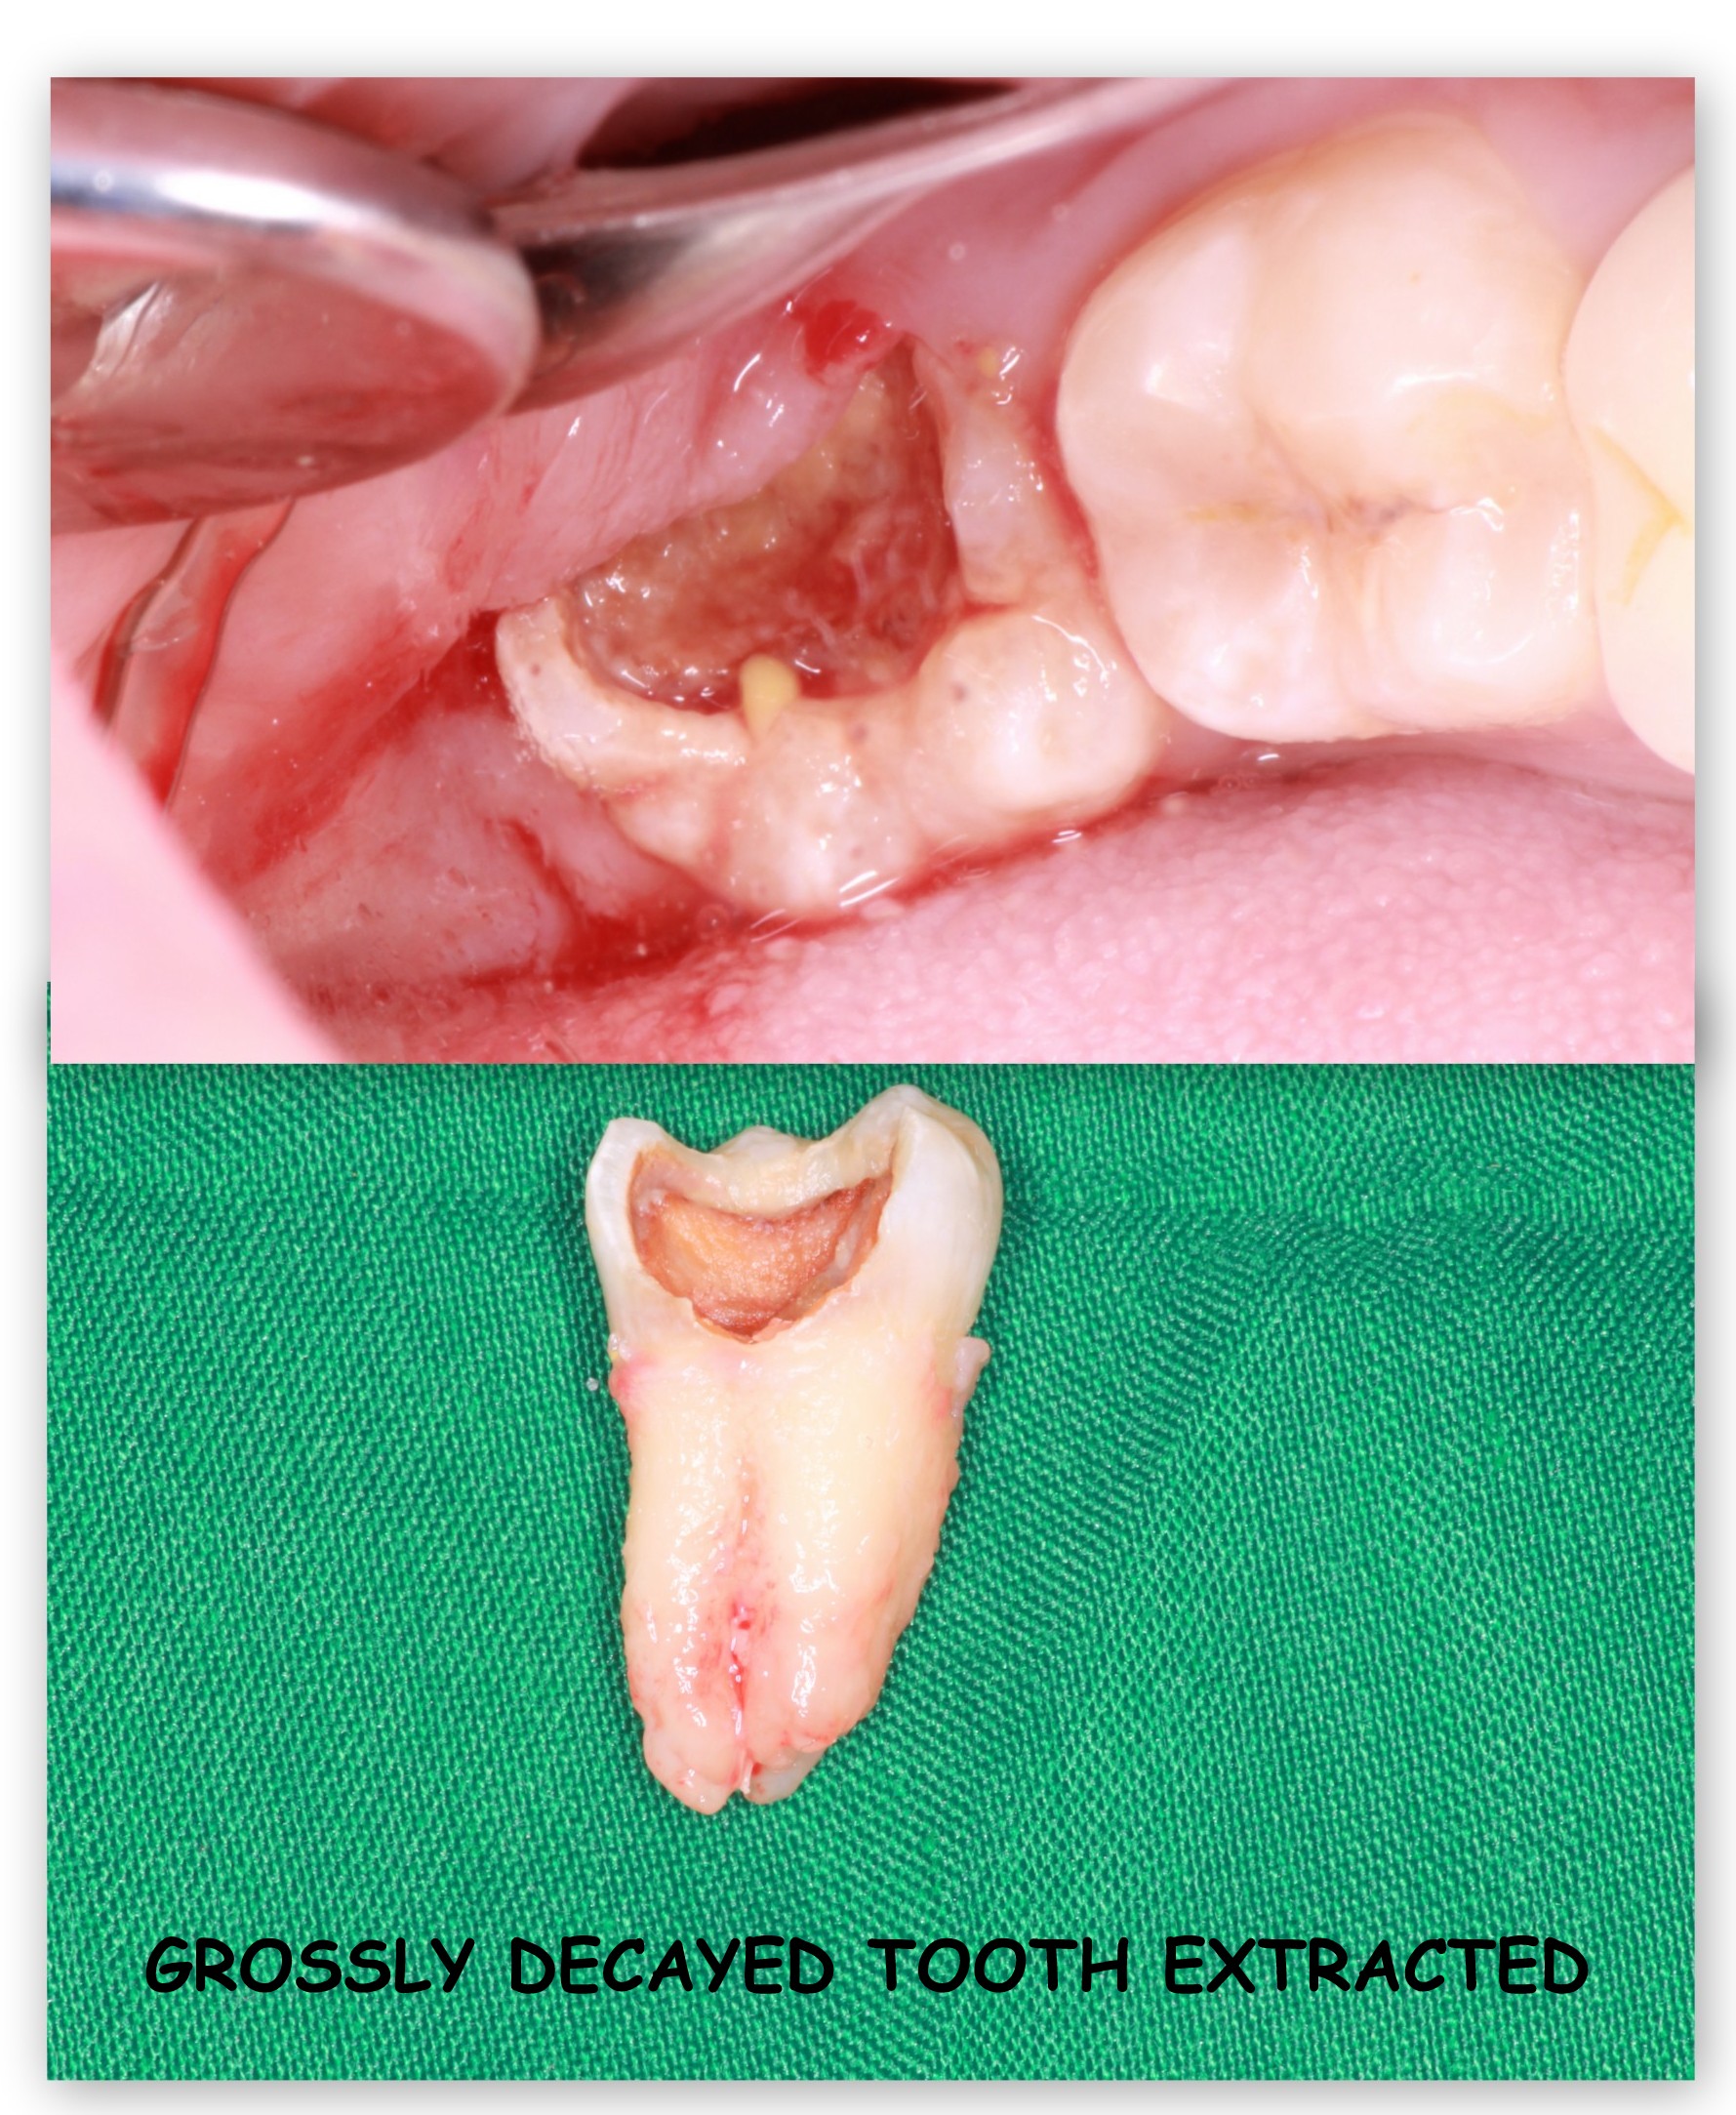

Wisdom tooth extraction is recommended in cases of decayed, un-erupted or wrongly erupting last molar teeth. Symptoms of the above may be pain while opening their mouth or chewing food, severe or dull nagging tooth ache, ear/jaw pain, difficulty in eating due to swelling of gums around the tooth.

- Tilted or wrongly erupting wisdom teeth are very difficult to clean and will most definitely get decayed if extraction is prolonged.

- Decay will spread to neighbouring teeth leading to cavities or even root canal.

- Swelling and infection around the tooth and gums may spread to the bone.